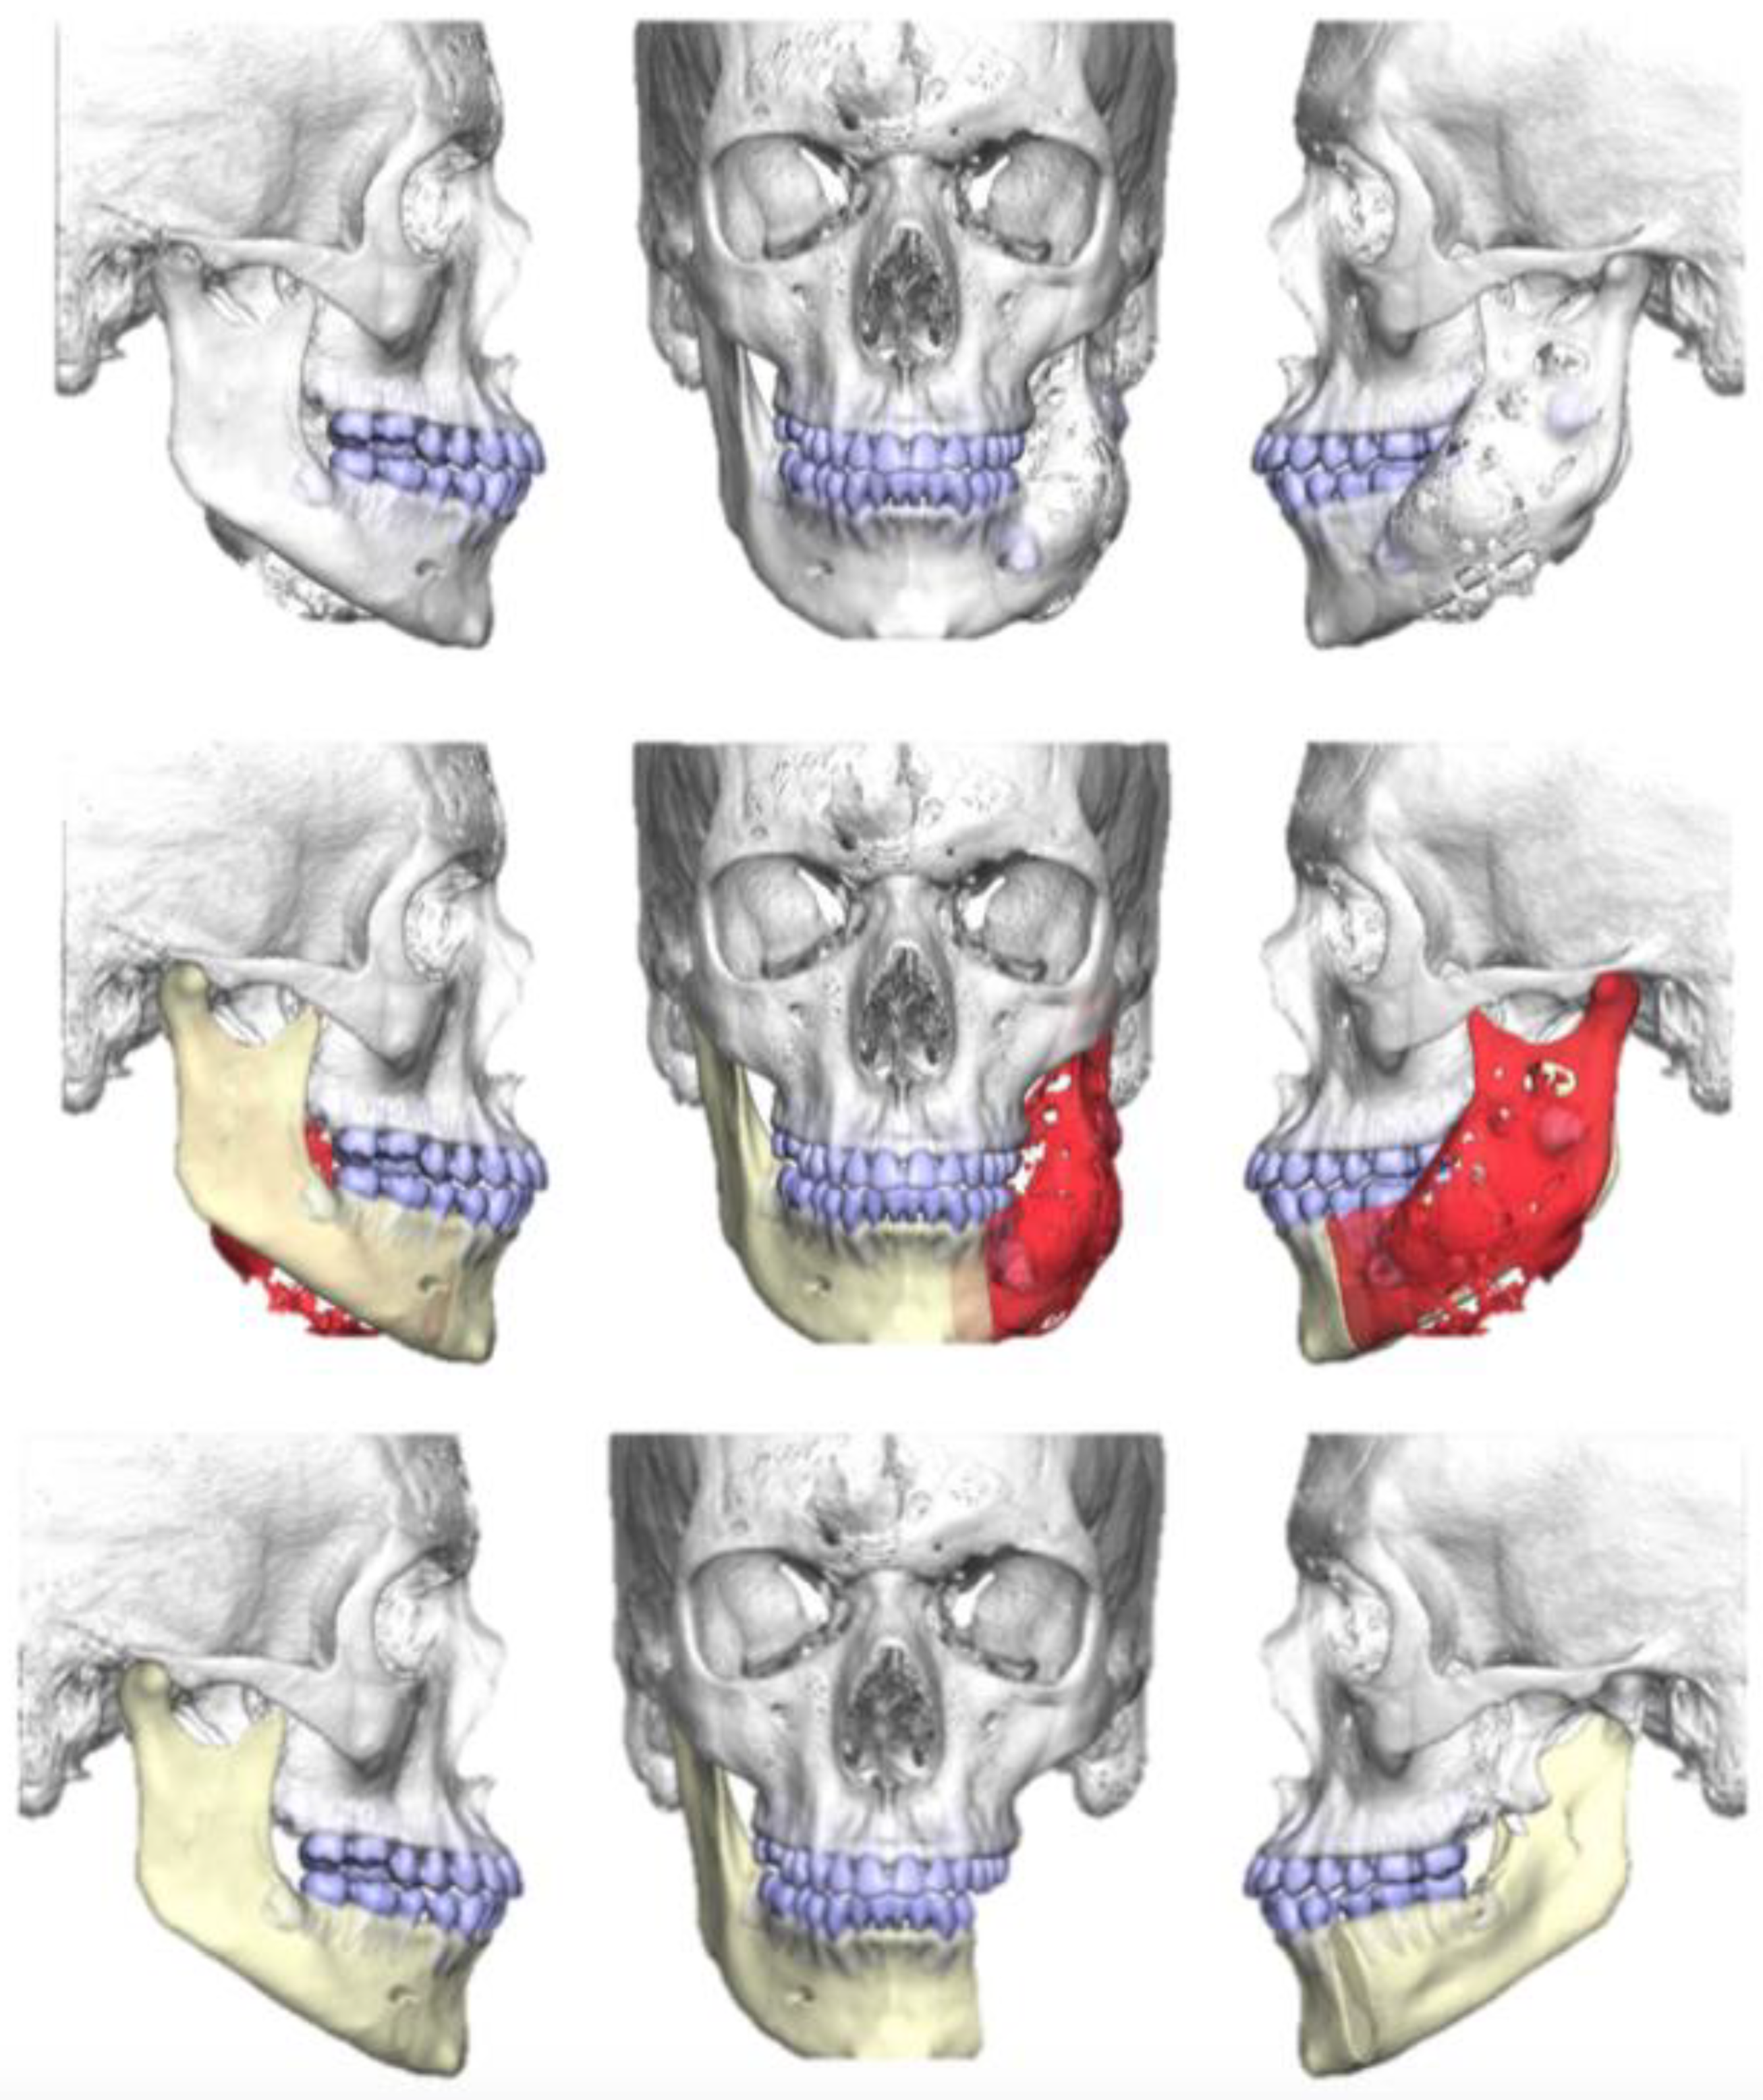

2.1. Case 1

2.2. Case 2